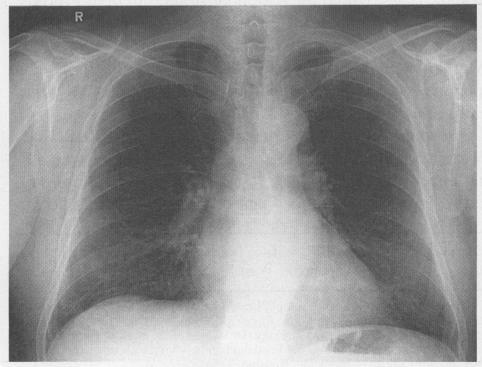

Isolated pulmonary metastases from prostatic adenocarcinoma.